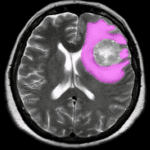

Phù Não | Bài giảng CĐHA

Phù não là khi dịch tích tụ xung quanh tổ chức não, gây ra sự gia tăng áp lực nội sọ, chia làm 3 loại:

– Phù độc tế bào (Cytotoxic Oedema)

+ Do rối loạn chuyển hóa trong tế bào, rối loạn hoạt động kênh natri phụ thuộc ATP. Thường thấy trong thiếu máu nuôi cấp tính ở não do bệnh lý tim mạch hoặc chấn thương sọ não. Hàng rào máu não không bị tổn thương, chủ yếu là do rối loạn chuyển hóa bên trong tế bào. Các tế bào hình sao bị phình to lên, nhất là 3 ngày đầu sau chấn thương. Các tế bào thần kinh bị tổn thương đáng kể từ ngày thứ 3 đến ngày thứ 11…